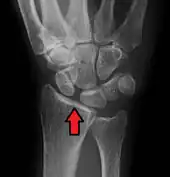

Static scapholunate dissociation

X-ray images indicate scapholunate ligament instability when the scapholunate distance is more than 3 mm, which is called scapholunate dissociation.[7] A static scapholunate instability is generally readily visible, but a dynamic scapholunate instability can only be seen radiographically in certain wrist positions or under certain loading conditions, such as when clenching the wrist, or loading the wrist in ulnar deviation.[6]

In order to diagnose a SLAC wrist you need a posterior anterior (PA) view X-ray, a lateral view X-ray and a fist view X-ray.[8] The fist X-ray is often made if there is no convincing Terry Thomas sign. A fist X-ray of a scapholunate ligament rupture will show a descending capitate bone. Making a fist will give pressure at the capitate, which will descend if there is a rupture in the scapholunate ligament.